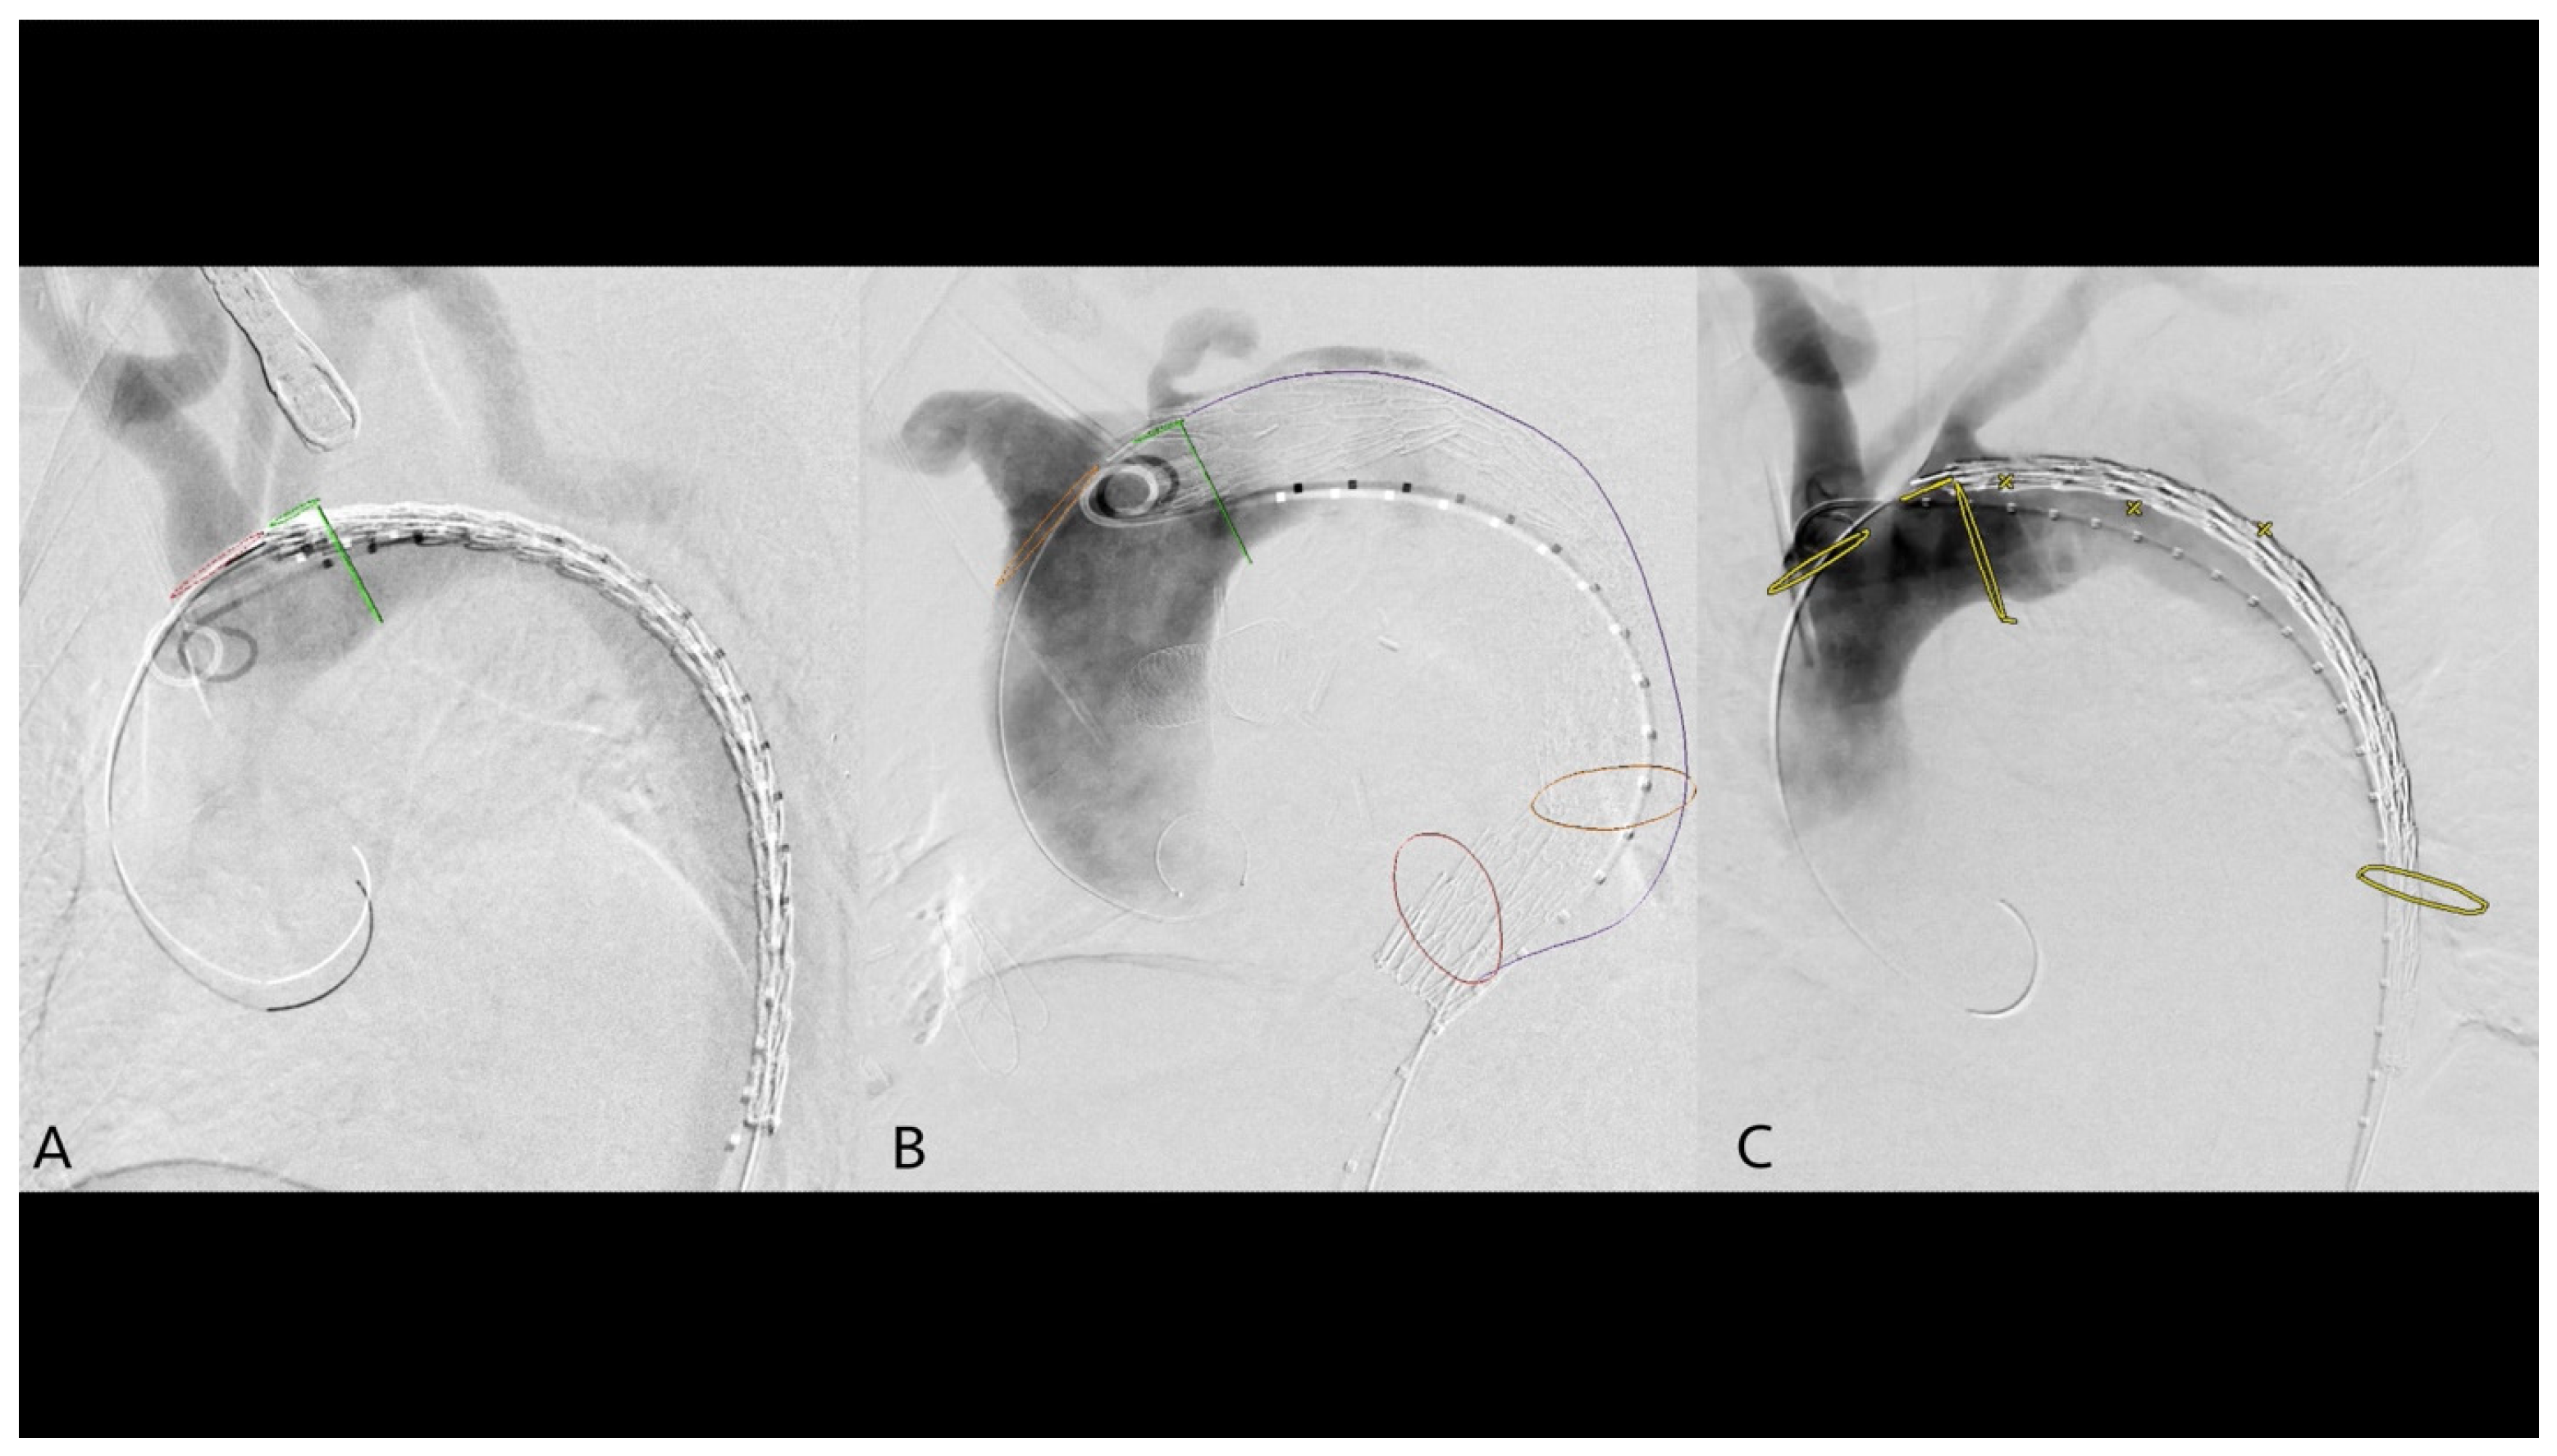

2.4. 2D3D Fusion Technique

2.5. 3D3D Fusion Technique